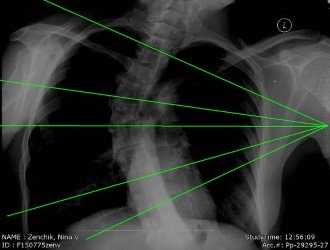

Для оценки кифоза Шейермана необходимы тщательно собранный анамнез, физикальное обследование и рентгенограммы в боковой и передне-задней проекциях. Боковые рентгенограммы требуются при диагностике. Диагностическими критериями являются:

- Грубый гиперкифоз более чем 40 градусов.

- Передняя клиновидная деформация тела позвонка на 5 градусов или более (в трех или более соседних позвонках).

Также на рентгенограммах обнаруживаются:

- Неправильная форма у опорных площадок тел позвонков.

- Грыжи Шморля.

- Снижение высоты межпозвонкового пространства.

- Сколиоз.

- Спондилолиз / Спондилолистез.

- Грыжи дисков.